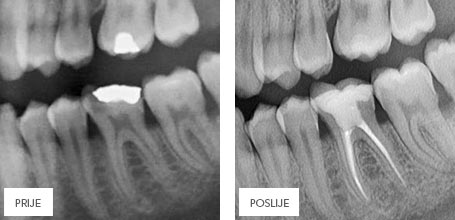

ЭНДОДОНТИЯ – ЛЕЧЕНИЕ КОРНЕВЫХ КАНАЛОВ ЗУБА

В результате кариеса или разрушения зуба бактериям открывается доступ к корневому каналу (пульпе), что ведет к воспалению, а иногда и к некрозу, которые могут распространиться и на соседние ткани. Если такой процесс уже начался, то необходимо удалить из канала воспаленую или некротичную ткань, чтобы предотвратить ослабление соседних тканей и потерю зуба. Такое лечение называется эндодонтическим (терапия каналов зуба), которое может быть проведено вручную или с помощью специальной аппаратуры.

После обработки и очищения каналов, они заполняются специальной пастой и гуттаперчевыми штифтами, с помощью которых каналы герметически закрываются и дальнейшее проникновение бактерий и возникновение инфекции становится невозможным.

Зубы с удаленной пульпой (зубным нервом) становятся хрупкими и под воздействием жевательных действий быстрее разрушаются, поэтому часто рекомендуется укреплять такие зубы керамическими пломбами.